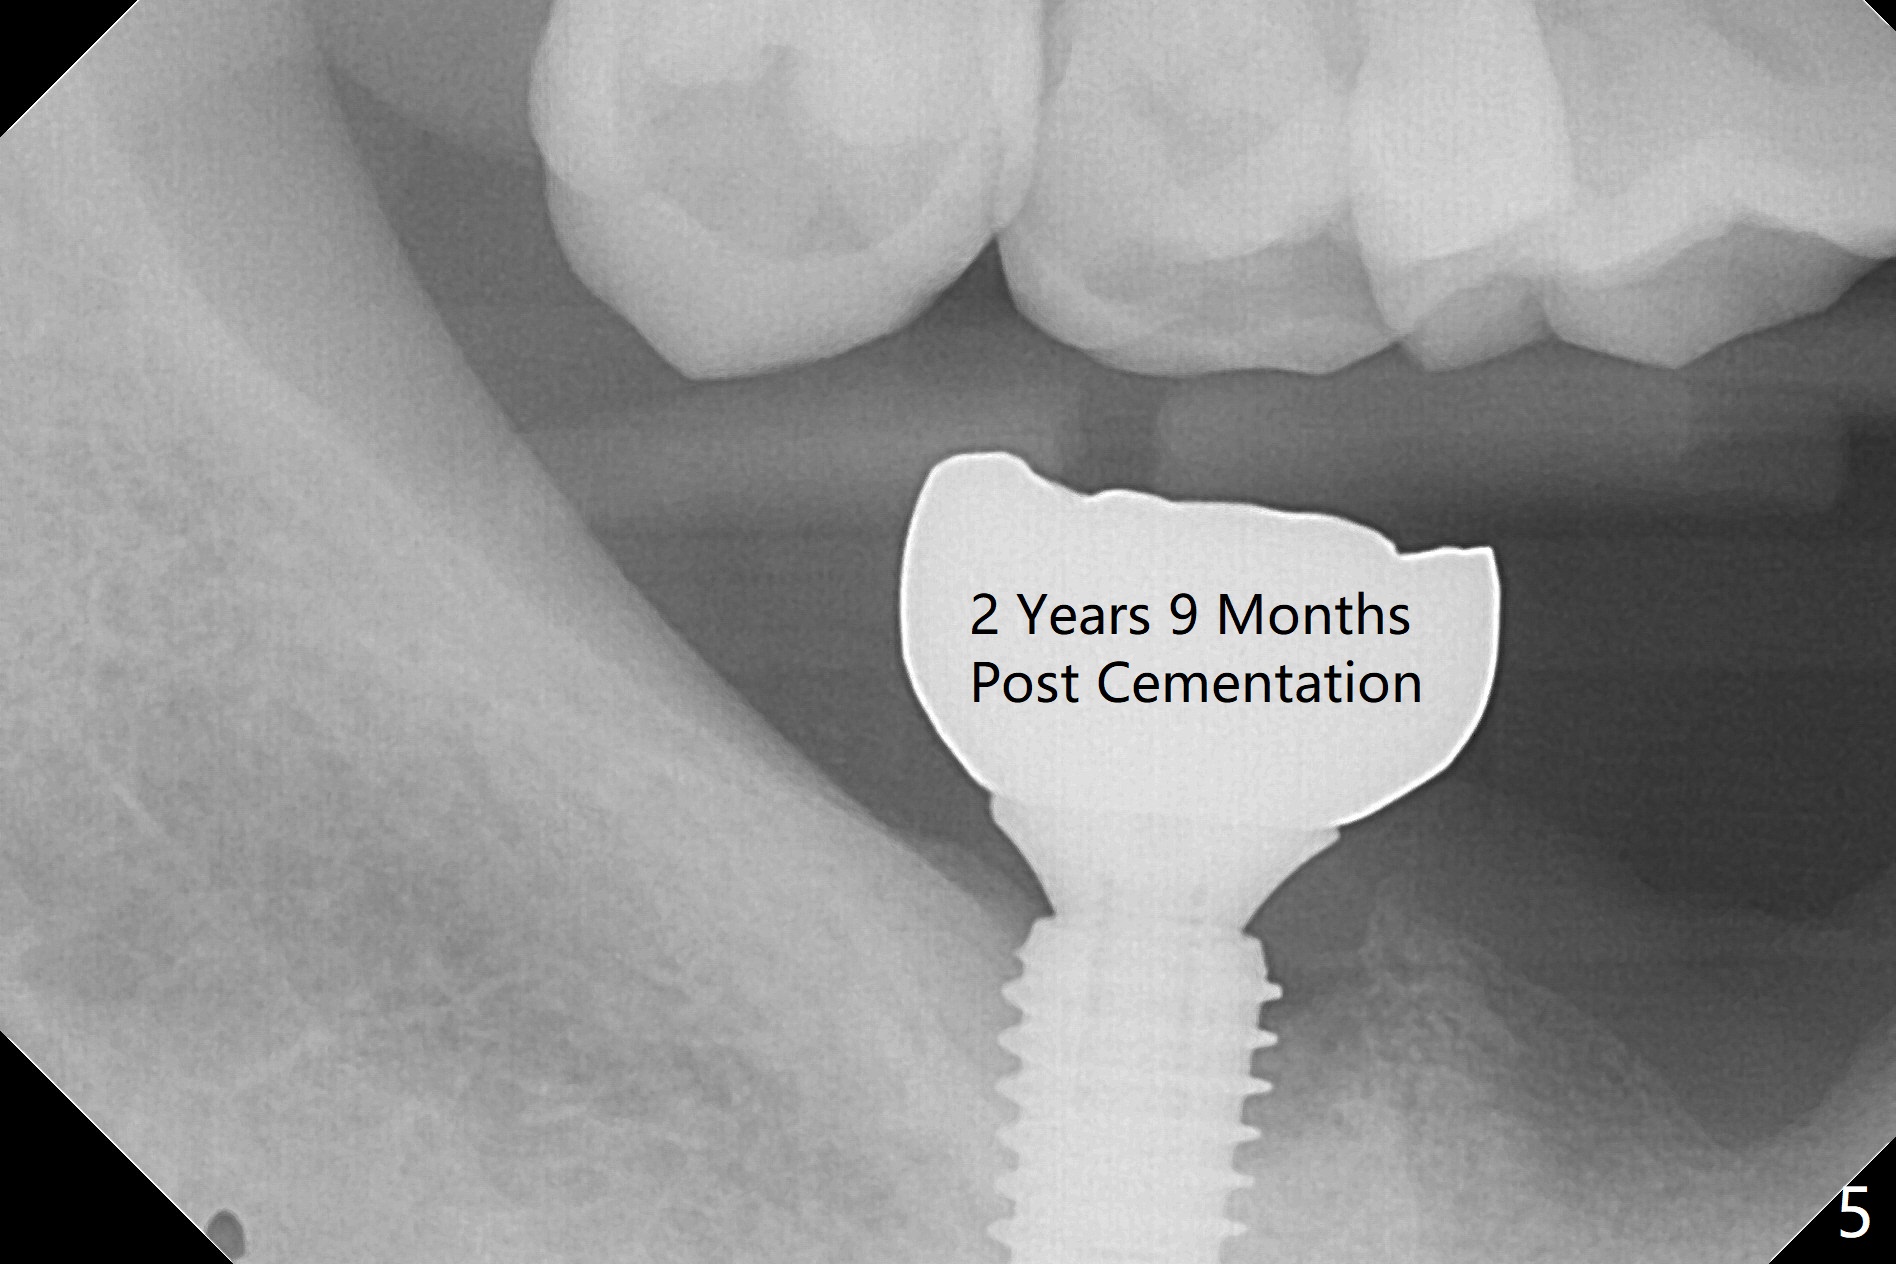

The leukoplakia at the sites of #31 and 32 is most likely related to smoking and the supraerupted teeth #1 and 2 (Fig.0 ^).  After osteotomy for 11.5 mm at #31 (Fig.1), it appears that the bone height is not as much as expected.  The last two drills for sequential osteotomy are 4.3x13 and 4.8x11.5 mm.  A 5x11.5 mm UF implant is placed slightly subcrestal with insertion torque > 50 Ncm (Fig.2).  Following placement of 6.5x2 mm healing abutment, the opposing tooth needs adjustment for height.  Orthodontic intrusion of the opposing tooth is scheduled 2 days later.  It is accidental to find root fracture of the mesial root of the tooth #30 (Fig.1 <).  There is minimal bone resorption coronally 5 months postop (Fig.3).  A provisional is fabricated at #31 to assist in intrusion of the tooth #2.  A crown is cemented 11.5 months postop (Fig.4); the leukoplakia at #31 seems to lessen.  The tooth #30 is lost during the pandemic, followed by looseness of the crown and abutment at #31.  When the complex is reseated, the occlusal scheme is changed, suggesting incomplete seat of the abutment earlier (Fig.5).